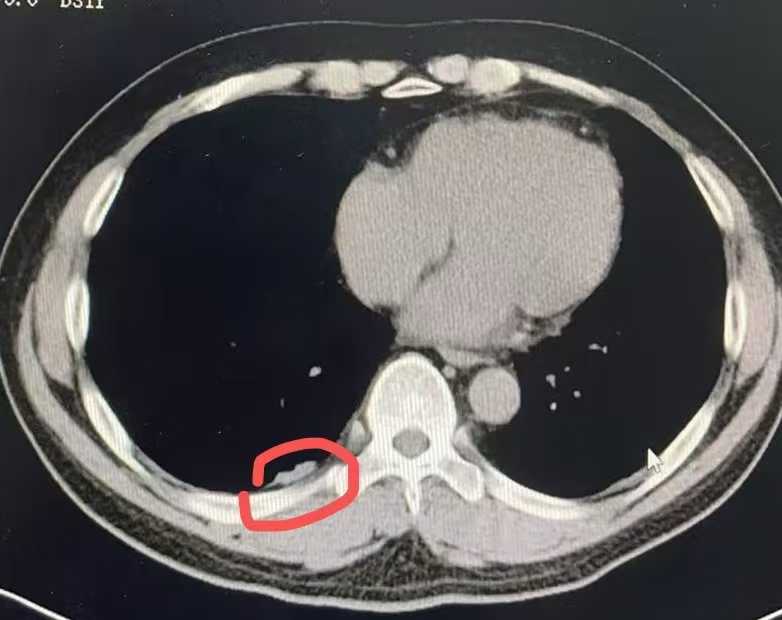

首先,医疗技术与设备的先进性是不可或缺的支柱。 龙华肾癌治疗已从传统开放手术迈向微创时代,如腹腔镜或机器人辅助手术,能显著减少创伤、加快恢复。广州复大肿瘤医院引进了国际前沿的达芬奇手术机器人系统,配合高清影像导航,实现毫米级精准操作。针对复杂病例,医院还整合了靶向药物与免疫疗法,通过*个性化基因检测*制定方案,要让治疗有的放矢。临床数据显示,其龙华肾癌手术成功率高达85%,让患者术后生活品质大幅提升。这些硬核技术背后,体现的是医院对创新医疗的持续投入,而非简单的设备堆砌——它让治疗更可靠、高效,成为患者康复的坚实后盾。